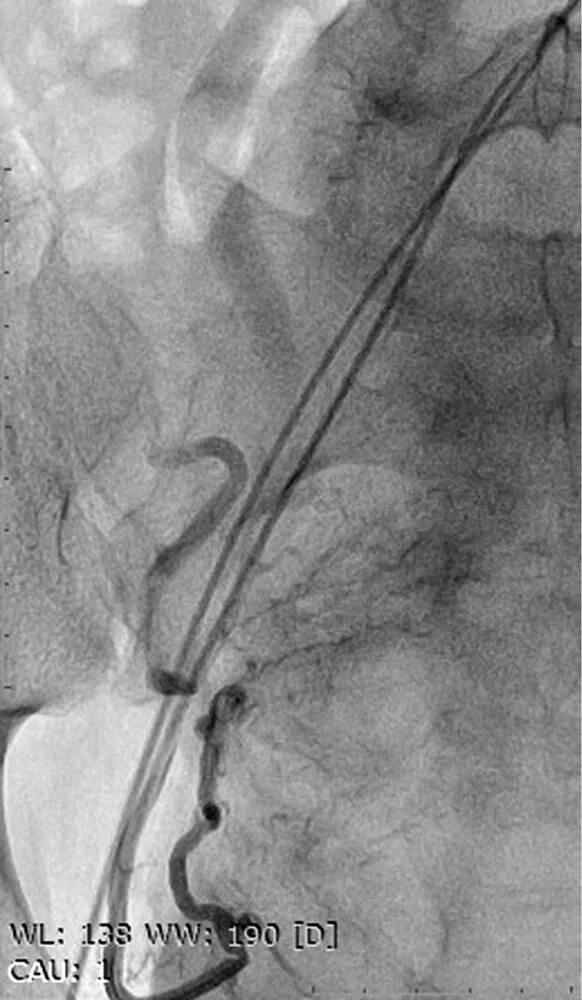

Операция эмболизация маточной артерии